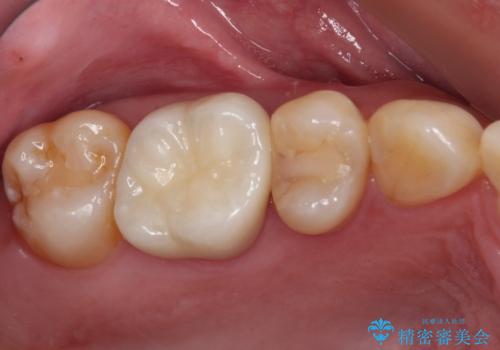

健全歯質が多いため、インレーおよびむし歯を除去した上で知覚過敏を緩和させる処置を行うことが望ましいと判断されましたが、知覚過敏の症状が一向に改善されないため、全体をセラミッククラウンで補綴することとしました。

セラミッククラウンを装着する前に仮歯を装着しましたが、その時点で強い痛みはほぼ改善され、セラミッククラウン装着後には痛みはもちろん、しみる症状も感じることがなくなりました。